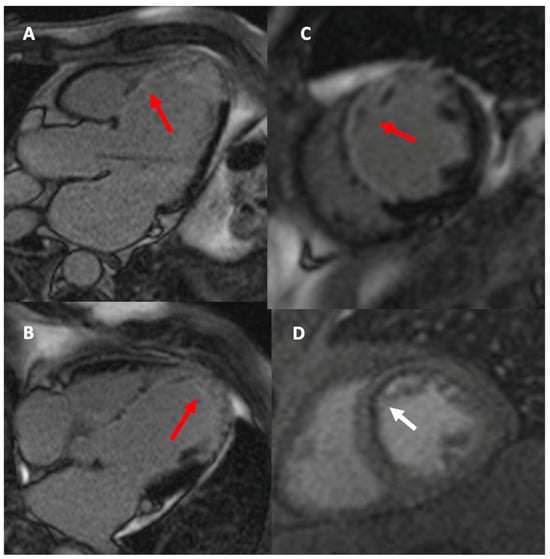

- Pegg, T.J.; Selvanayagam, J.B.; Francis, J.M.; Karamitsos, T.D.; Maunsell, Z.; Neubauer, S.; Taggart, D.P. A randomized trial of on-pump beating heart and conventional cardioplegic arrest in CABG patients with impaired ventricular function using CMR. Circulation 2008, 118, 2130–2138. [Google Scholar] [CrossRef] [PubMed]

- Thielmann, M.; Hunold, P.; Böhm, C.; Massoudy, P.; Jakob, H. Magnetic resonance imaging in CABG—Improvement of global and segmental function in patients with severely compromised LV function. Vasc. Health Risk Manag. 2007, 3, 763–768. [Google Scholar]

- Zhao, Y.; Fu, W.; Hou, X.; Zhang, J.; Biekan, J.; Zhang, H.; Wang, H.; Dong, R. Myocardial infarct size for predicting improvements in cardiac function in ICM patients after CABG. Quant. Imaging Med. Surg. 2023, 13, 7814–7827. [Google Scholar] [CrossRef]

- Zhuang, B.; Li, S.; Wang, H.; Chen, W.; Ren, Y.; Zhang, H.; Sun, Z.; Xu, L. Incremental prognostic value of CMR in patients with severe LV dysfunction undergoing CABG. Int. J. Cardiovasc. Imaging 2024, 40, 2057–2068. [Google Scholar] [CrossRef]

- Bernhardt, P.; Spiess, J.; Levenson, B.; Pilz, G.; Höfling, B.; Hombach, V.; Strohm, O. Combined assessment of myocardial perfusion and late gadolinium enhancement in patients after percutaneous coronary intervention or bypass grafts: A multicenter study of an integrated cardiovascular magnetic resonance protocol. JACC Cardiovasc. Imaging 2009, 2, 1292–1300. [Google Scholar] [CrossRef] [PubMed]